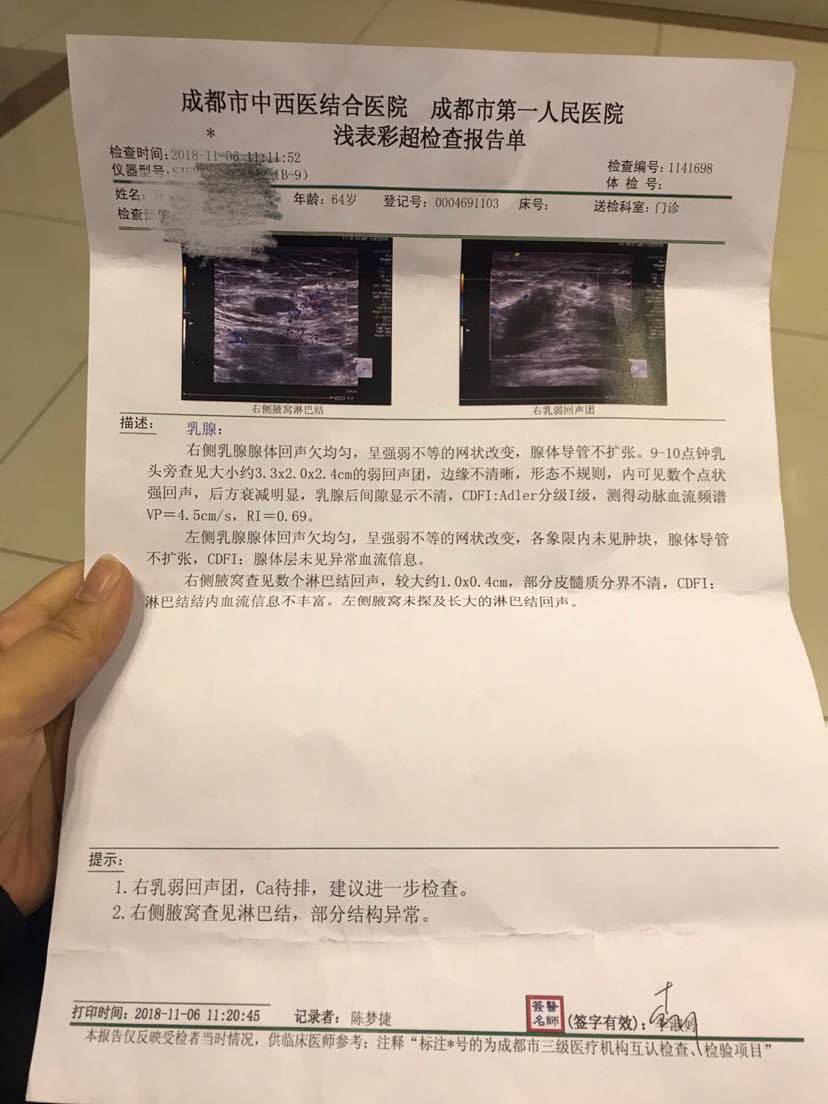

这是第一家医院做的检查

B超显示有不规则结节,ca待排,就是疑似乳癌了。最终的金标准就是取样做病理,赶紧带你妈妈住院尽快手术吧!规范系统治疗,没问题的